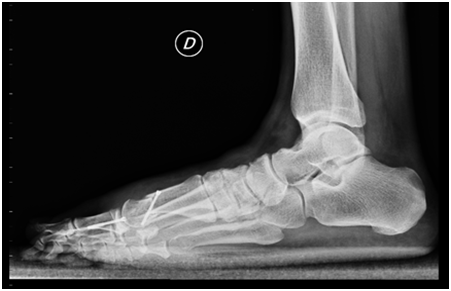

Figure 4 Postoperative X-rays 3 months after surgery.